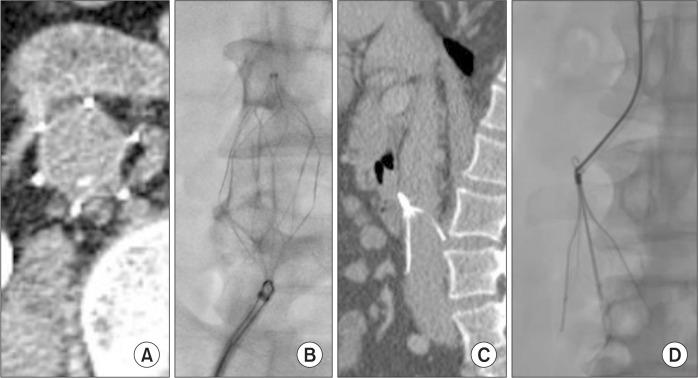

Implementing an inferior vena cava (IVC) filter is a relatively safe procedure but potential negative long-term effects. The complications for filter retrieval have been noted. We examined filter characteristics on pre-retrieval computed tomography (CT) that were associated with complicated retrieval (CR) of IVC filters.

A retrospective review of IVC filter retrievals between January 2008 and June 2014 was performed to identify patients who had undergone a pre-retrieval CT for IVC filter retrieval. CR was defined as the use of nonstandard techniques, procedural time over 30 min, filter fractures, filter tip incorporation into the IVC wall, and retrieval failure. Pre-retrieval CT images were evaluated for tilt angle in the mediolateral and anteroposterior directions, tip embedding into the IVC wall, degree of filter strut perforation, and distance of the filter tip from the nearest renal vein.

Of seventy-six patients, twenty-four patients (31.6%) with CRs and 56 patients (73.7%) with non-CR were evaluated for pre-retrieval CT. For IVC filter retrieval with a dwelling time of over 45 days, a tilt of over 15 degrees, the appearance of tip embedding and grade 2 perforation were associated with CR on multivariate analysis. However, for IVC filter retrievals with a dwelling time of less than 45 days, there were no factors associated with CR.

Pre-retrieval CTs may be more effective for IVC filters with a dwelling time of over 45 days. Therefore, a pre-retrieval CT may be helpful in predicting CR of IVC filters with long dwelling times.